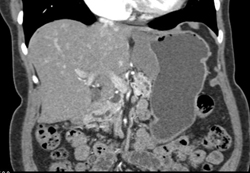

Diagnosis

Lipoma in Antrum